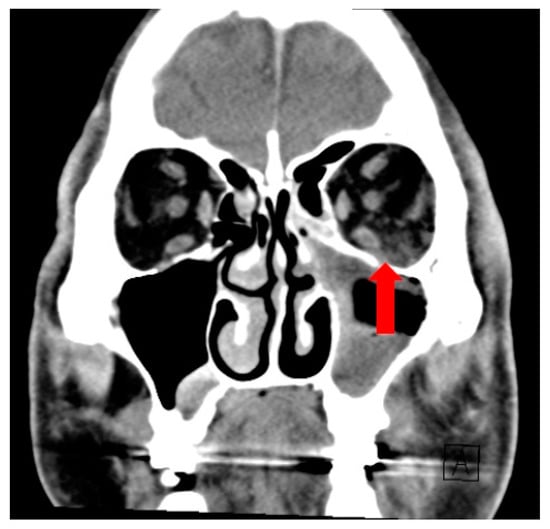

Soft tissue inflammation extended beyond the sinus to involve the orbit superiorly (Figure 2), infratemporal fossa laterally and subcutaneous tissue of the cheek anteriorly. The roots of the second and third maxillary molars were seen protruding into the maxillary sinus (Figure 3).

Figure 2.

Coronal CT image showing fat stranding in the left extra-conal orbital fat (red arrow).